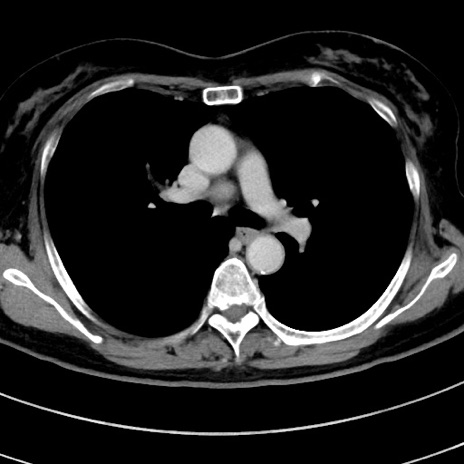

症例9(横断像)

【症例】 60歳代女性

【主訴】むかつき、みぞおちの痛み

【現病歴】3日前よりむかつきがあり、食事がとれない。

【既往歴】糖尿病

【身体所見】発熱なし、心窩部圧痛軽度あるも、腹膜刺激症状なし。

【データ】WBC 7400、CRP 1.92